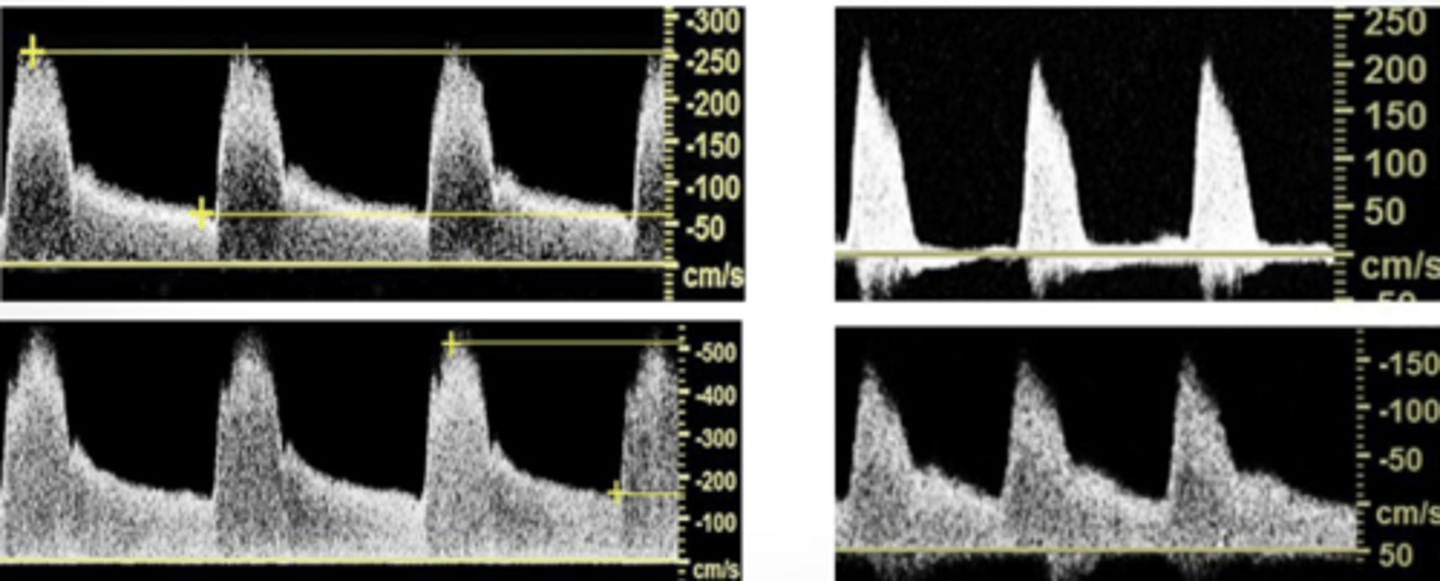

High Resistance

sharp upstroke/brisk downstroke

Intermediate Resistance

-sharp upstoke/brisk downstroke

-forward flow throughout

-end systolic notch

Low Resistance

broad downstroke and continual flow through out diastole

Normal High Resistance

-infra renal aorta, CIA, EIA, IIA

-SMA/IMA Fasting

-CFA, DFA, SFA, Pop, ATA, PTA, Pero

-subclavian, axillary, brachial, radial, ulnar

-external carotid

Normal Intermediate Resistance

-supra renal aorta

-common carotid

Normal Low Resistance

-celiac, renal, SMA, IMA post prandial

-internal carotid, vertebral artery

-hepatic and splenic arteries